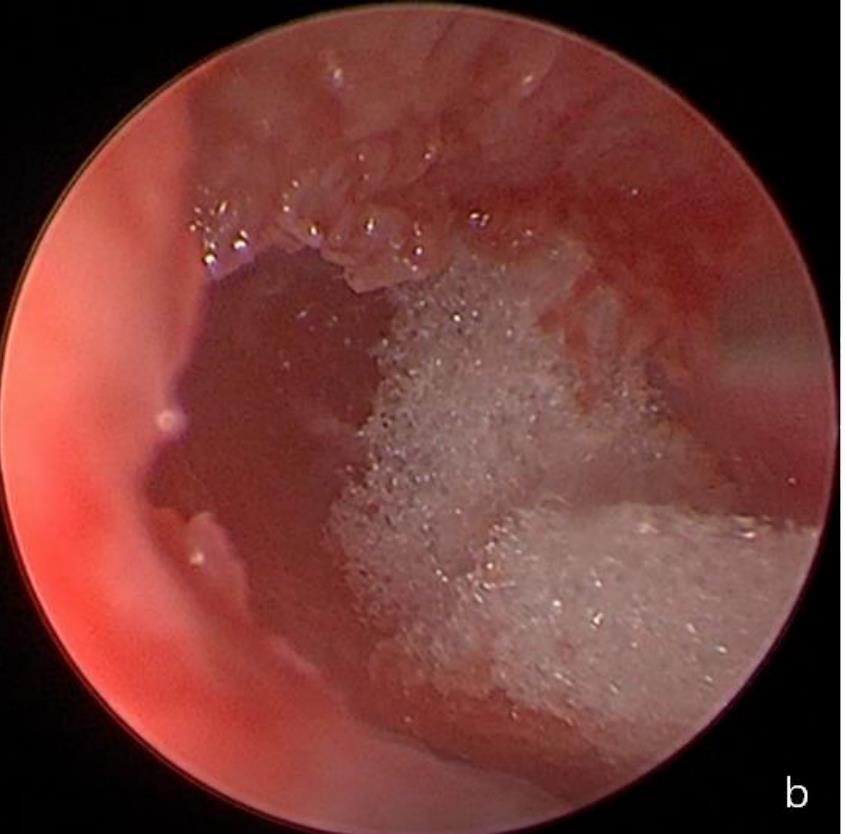

摘要:目的 探究一次性eyeMax洞察胰胆管成像系统辅助内镜逆行阑尾炎治疗术(ERAT)治疗阑尾炎的效果及安全性。方法 回顾性分析2023年4月-2024年9月在该院就诊,通过影像学或内镜检查确诊的54例非复杂性阑尾炎患者的临床资料。所有患者均行eyeMax洞察胆胰管成像系统辅助ERAT,于直视下观察阑尾腔,并通过冲洗、取石、扩张狭窄和支架引流等措施治疗阑尾炎。观察手术相关指标、术后疼痛程度、并发症发生情况、术后1年内复发率、结肠镜下表现、胰胆管成像系统下表现和胆胰管成像系统下治疗情况。结果 54例患者均顺利完成手术,技术成功率为100.0%,手术时间(60.6±27.9)min,住院时间(3.6±1.5)d;30例(55.6%)阑尾开口及周边黏膜充血水肿,2例(3.7%)可见脓液及污秽物流出;54例(100.0%)患者阑尾腔内壁充血水肿,51例(94.4%)可见腔内絮状物、脓液或脓苔附着,25例(46.3%)可见腔内粪石,15例(27.8%)可见管腔走形迂曲或狭窄。所有患者予以eyeMax洞察胰胆管成像系统治疗,简单灌洗54例,网篮取石20例,支架引流25例。术后VAS评分为0(0,0)分,明显低于术前的6(3,7)分,手术前后比较,差异有统计学意义(Z = -6.24,P = 0.000)。所有患者术后症状均暂时缓解,术中及术后未发生穿孔和大出血等严重不良事件。随访1年内,阑尾炎复发率为20.4%(11/54)。结论 EyeMax洞察胆胰管成像系统辅助ERAT是治疗非复杂性阑尾炎安全和有效的疗法,其具有直视下精准操作、保留阑尾功能、症状快速缓解、无X线暴露和精准诊疗阑尾病变等优势。值得应用于临床。